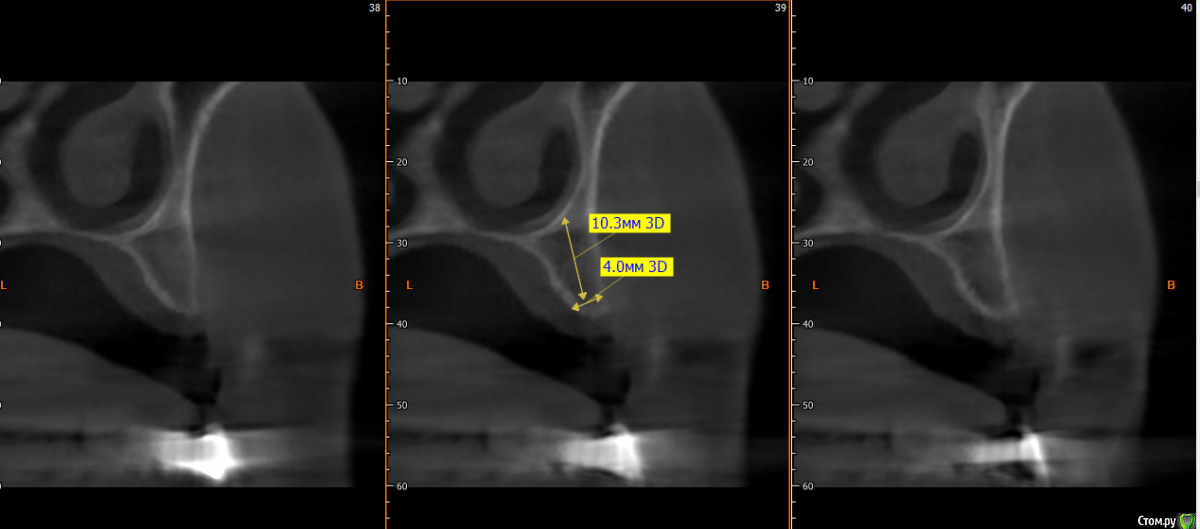

kramer Опубликовано 15 мая, 2019 Поделиться Опубликовано 15 мая, 2019 Коллеги, здравствуйте. Нужен совет. Ситуация: пациентка 70 лет (родственница), давно носила бюгельный протез, и вот одному из опорных зубов пришел конец. КТ ниже, фотографии завтра добавлю. Рассматриваю вариант изготовления несъемного протеза на 4 имплантатах. Опыта все-на-4 нет. Поэтому хотелось бы по крайней мере собрать информацию, возможна ли такая опция. Особенно волнует 2 момента: 1) Отсутствует вертикальная атрофия альвеолярного отростка во фронтальном отделе. Линия улыбки низкая. Предположим, окончательный протез будет м\к или циркон. Означает ли это, что редукцию кости делать необязательно? (правда там и редуцировать особо некуда). 2) В области 14 и 24 ширина гребня 3,5-4 мм. Что делать с этим? Оставлять пришеечную часть винта не покрытым костью небно или пытаться каким-то образом конденсировать кость? 14122224 Ссылка на комментарий

Smileee Опубликовано 16 мая, 2019 Поделиться Опубликовано 16 мая, 2019 Я бы везде установил 3.5, в области 24 немного редуцировал бы кость по вертикали. Все импланты максимально небно. Ссылка на комментарий

kramer Опубликовано 17 мая, 2019 Автор Поделиться Опубликовано 17 мая, 2019 не надо там ничего редуцировать, само резорбируется после удаления на 1-2 мм. все на 4-х и счастья вашей родственницеСпасибо, что делать с узким гребнем? Максимально глубить? Ссылка на комментарий